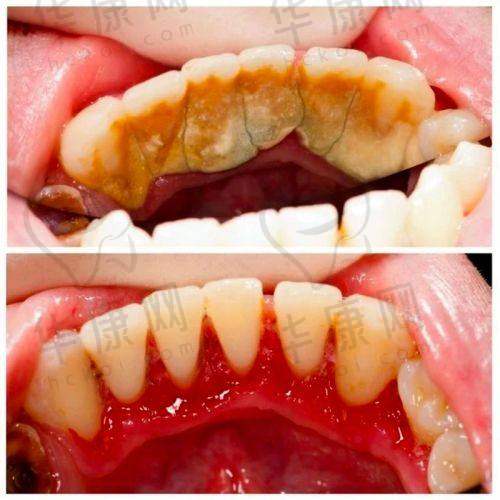

龙岩博恩口腔的超声波洁牙价格以148元起,不过实际价格会因多种因素产生波动。在2025年4月3日的信息显示,其超声波洁牙含抛光、喷砂仅52元起,定期护理更为划算。在2024年不同时间也有不同价格体现,如2月19日提到超声波抛光洁牙50元起,超声波喷砂洁牙208元起;11月7日洗牙50元起,喷砂洁牙200元起等。这些价格差异主要取决于洁牙方式、是否包含附加服务以及个人口腔状况等。例如,如果口腔牙结石较多、情况复杂,可能需要更精细的洁牙操作,价格就会相对高一些。

龙岩博恩口腔的医生团队技术扎实。他们都经过专精的培训和长期的实践,具备丰富的超声波洁牙经验。在洁牙过程中,医生能够精细地操作仪器,利用超声波振动原理,有效去除牙结石、牙菌斑等顽固污渍,同时较大程度减少对牙齿的损伤。医生还会根据患者的口腔实际情况,制定个性化的洁牙方案。比如对于牙齿敏感的患者,会采用更温和的洁牙方式和参数设置。此外,医生在洁牙后还会为患者提供专精的口腔护理建议,帮助患者更好地维护口腔健康。